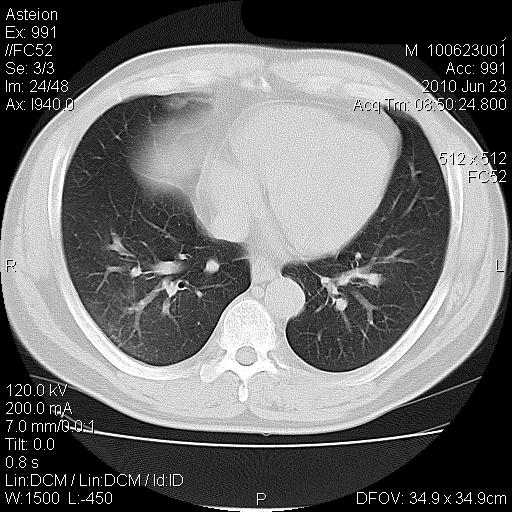

男 41岁 因发烧38-39度 这几天消炎治疗

化验结果 中性粒细胞比率升高(80.9) 淋巴细胞比率下降(10.2) 红细胞压积下降(33.4)

血小板平均分布密度升高(18.9)

双肺炎性灶【密度高 局限 考虑金葡菌 产血浆凝固酶所致】

病灶位于两上肺及右肺下叶背段,建议抗炎治疗后复查;结核不排外。

双肺炎性渗出病变,以右下肺为著。考虑金葡菌感染。

两肺多发结节斑块影,右下见支气管气相,支持两肺多灶性感染,抗炎治疗后复查。

双肺多发大小不等的团片状病灶,周围较模糊可见晕征,未见明显分叶征,纵膈淋巴结未见肿大。

考虑炎性病变。

双肺多发大小不等的团片状病灶可见于肺部炎性肉芽肿,也可见于肺淋巴瘤、肺淋巴瘤样肉芽肿、肺结核、肺部肿瘤,本例的影像表现结合临床考虑肺部炎性病灶。